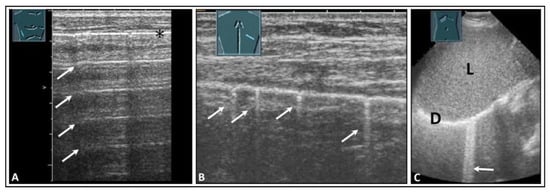

4. Pulmonary Edema and Acute Respiratory Distress Syndrome

5. Pneumonia